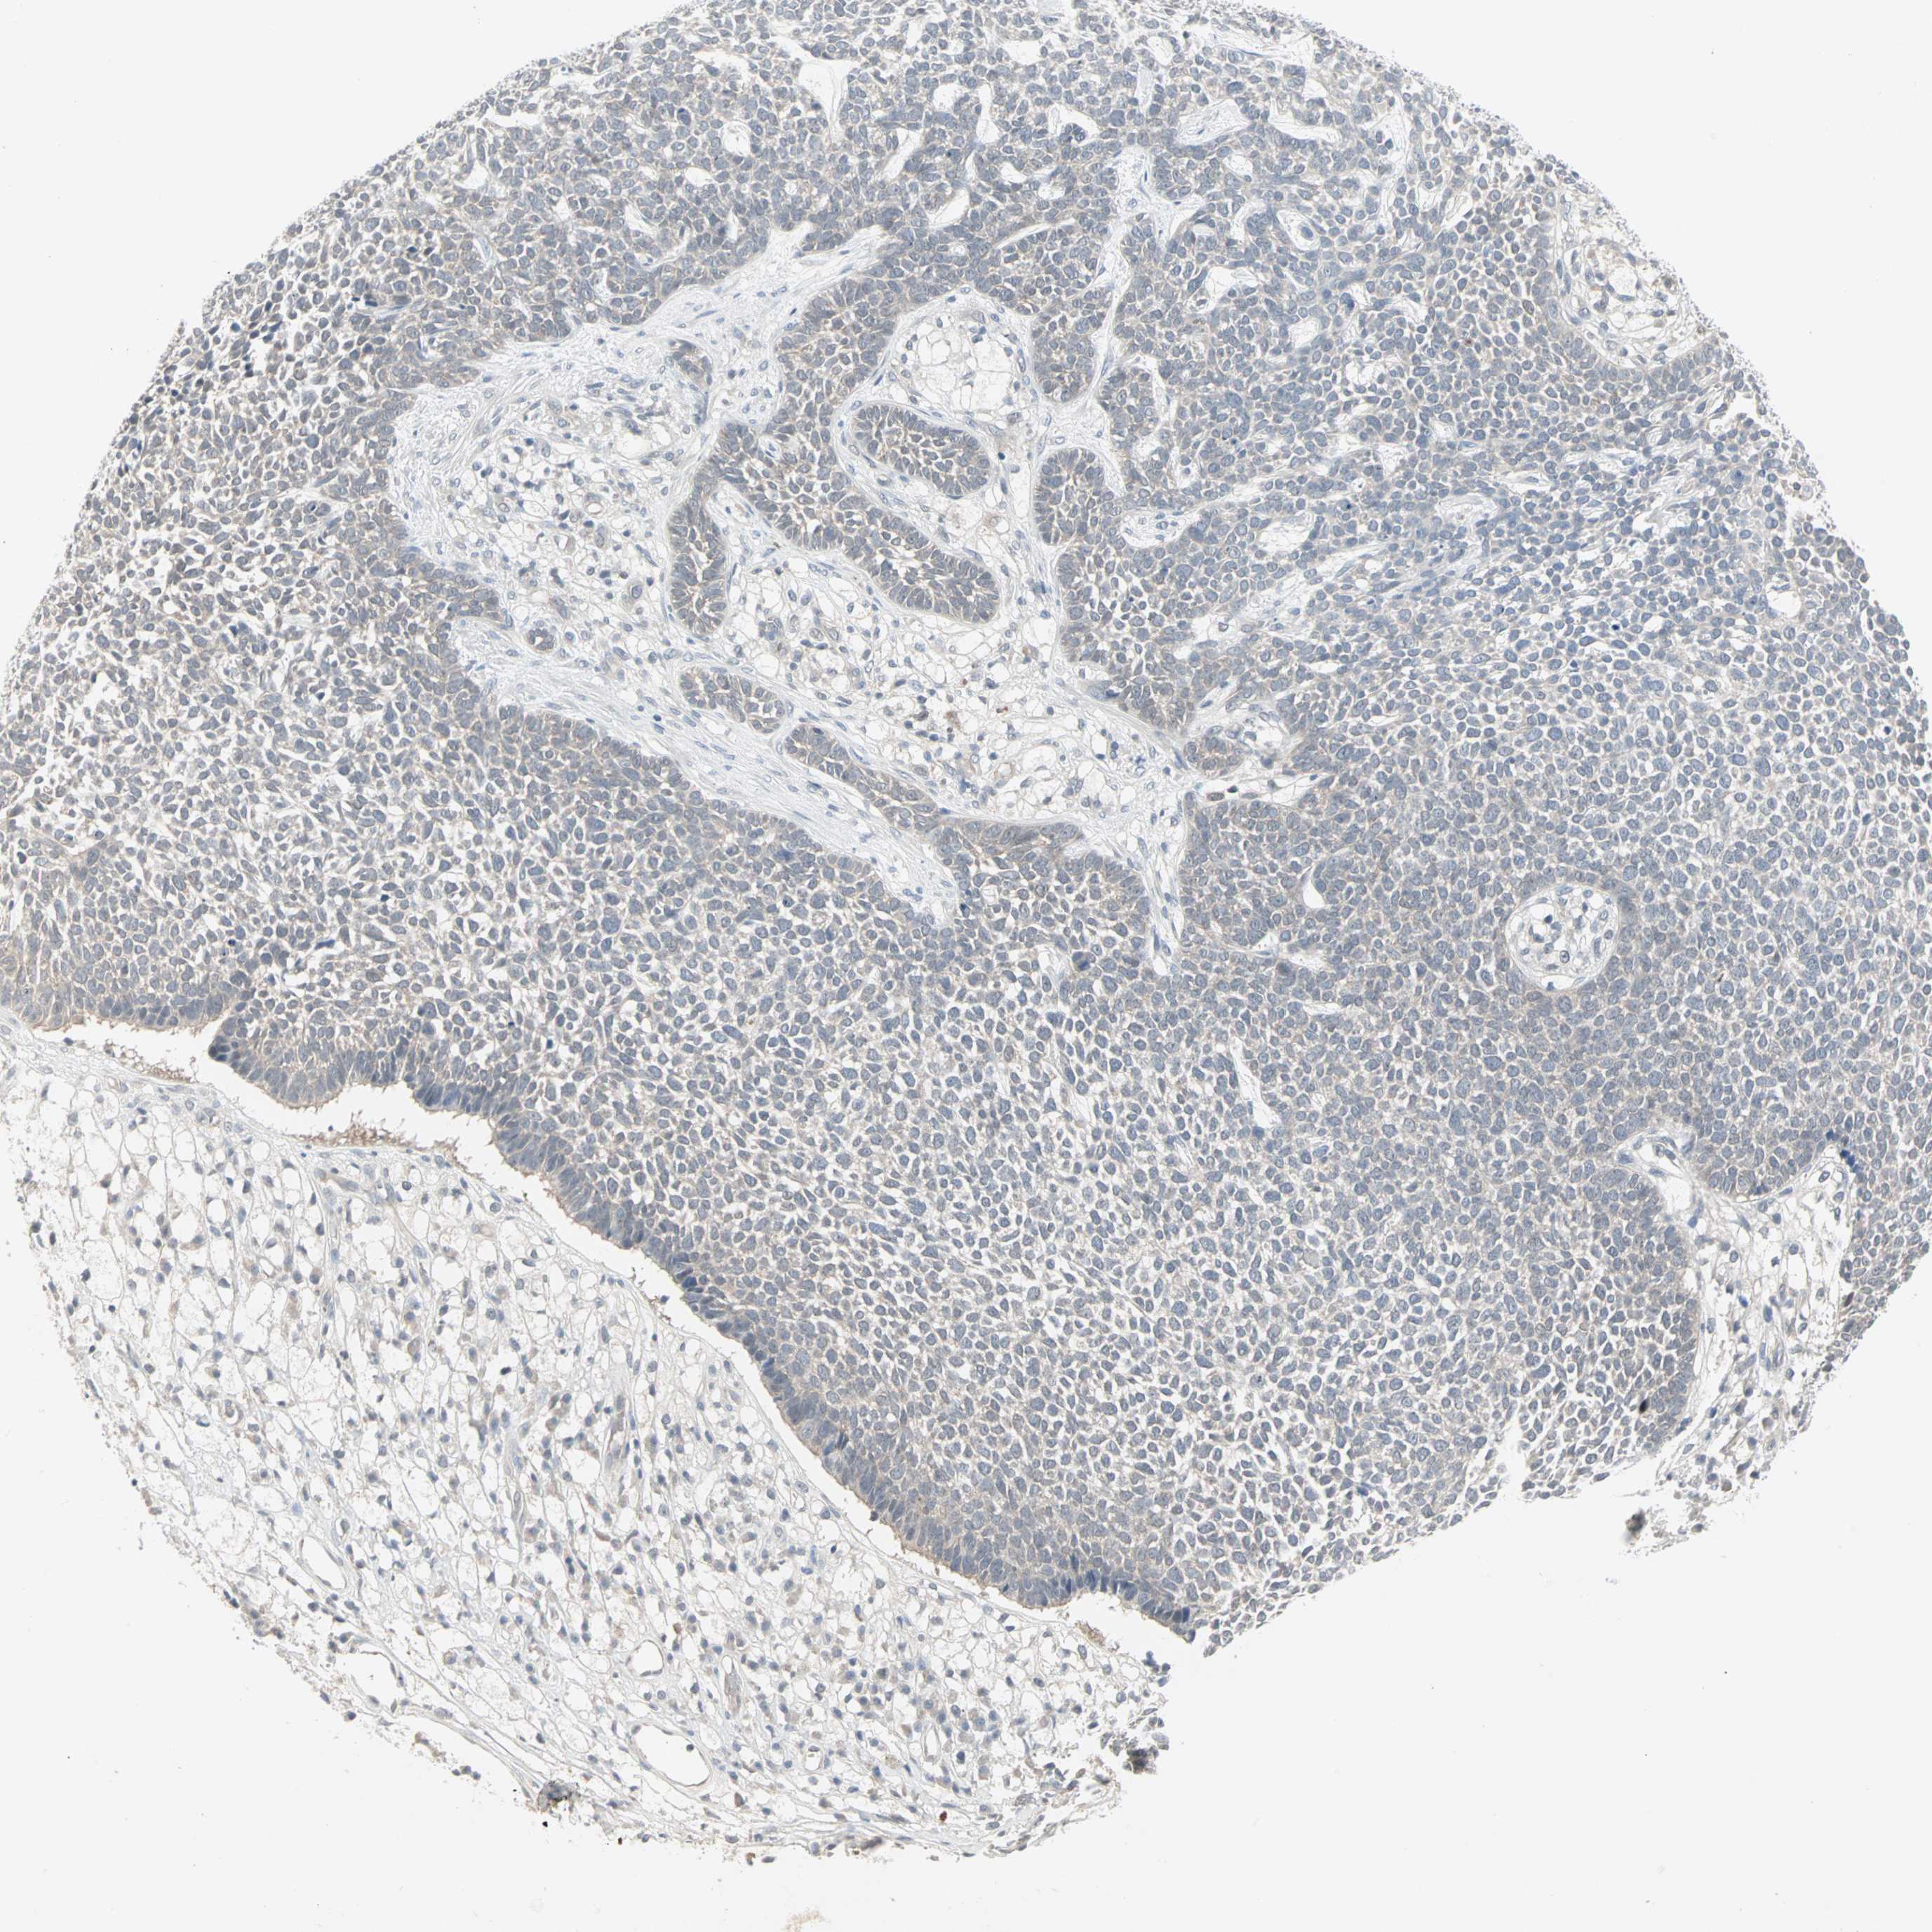

SKIN CANCER - Protein expressioni

A mouse-over function shows sample information and annotation data. Click on an image to view it in a full screen mode. Samples can be filtered based on level of antibody staining by selecting one or several of the following categories: high, medium, low and not detected. The assay and annotation is described here.

Each image is clickable and will lead to virtual microscopy that enables deeper exploration of all samples and also displays staining intensity scores, fraction scores and subcellular localization as well as patient and tissue information for each sample.

CAB035999

Squamous cell carcinoma, NOS